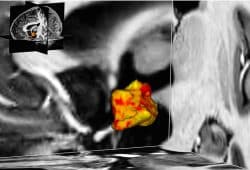

Ist der überforderte Hypothalamus schuld an vielen Depressionen?

Dass viele unserer seelischen Krankheiten mit direkten Veränderungen in unserem Körper zusammenhängen, wird selbst der Forschung erst nach und nach bewusst. Ein Grund ist natürlich, dass man erst so langsam lernt, wie unser Gehirn funktioniert und welche Folgen Veränderungen in einzelnen Regionen für unser Empfinden haben. Und Depressionen haben augenscheinlich auch Ursachen in unserem Gehirn. Ein Forschungsergebnis aus Leipzig.